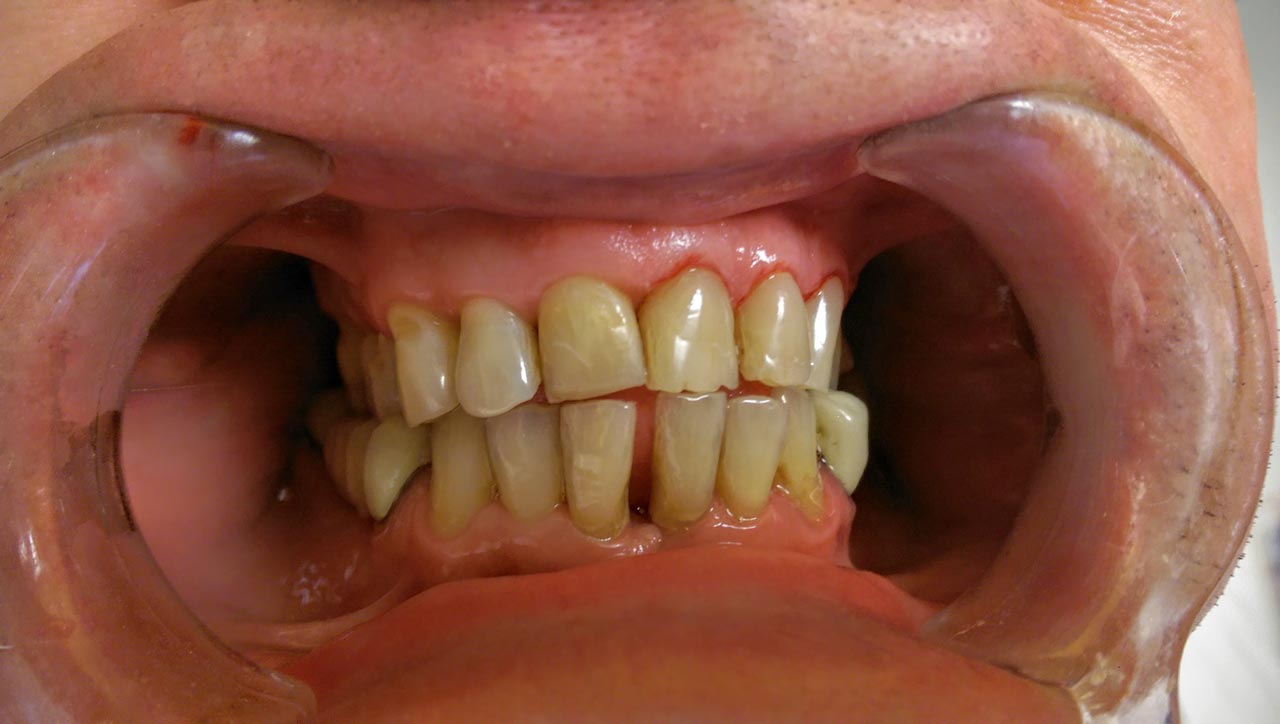

Fogmegtartó kezelések

Amennyiben pácienseink rendszeresen részt vesznek az éves szűrővizsgálaton, az esetek jelentős részében elkerülhetőek a foghúzások, szájsebészeti komolyabb beavatkozások, és csupán apróbb kezelésekre lehet szükség! Ilyenek például a szájhigiéniás kezelések, esztétikus tömések, betétek, koronák, gyökérkezelések.

Betegeink többféle (kémiai kötésű és fényre kötő) esztétikus tömés közül orvosainkkal együtt választják ki a megfelelőbbet! Fémmentes betéteinkkel, koronáinkkal természethűen tudjuk visszaállítani fogazatát. Gyökérkezeléseket csúcstechnológiás gépi tágítóval végezzük, aminek segítségével milliméter pontosan tudjuk bemérni a gyökértöméshez a csatorna hosszát.